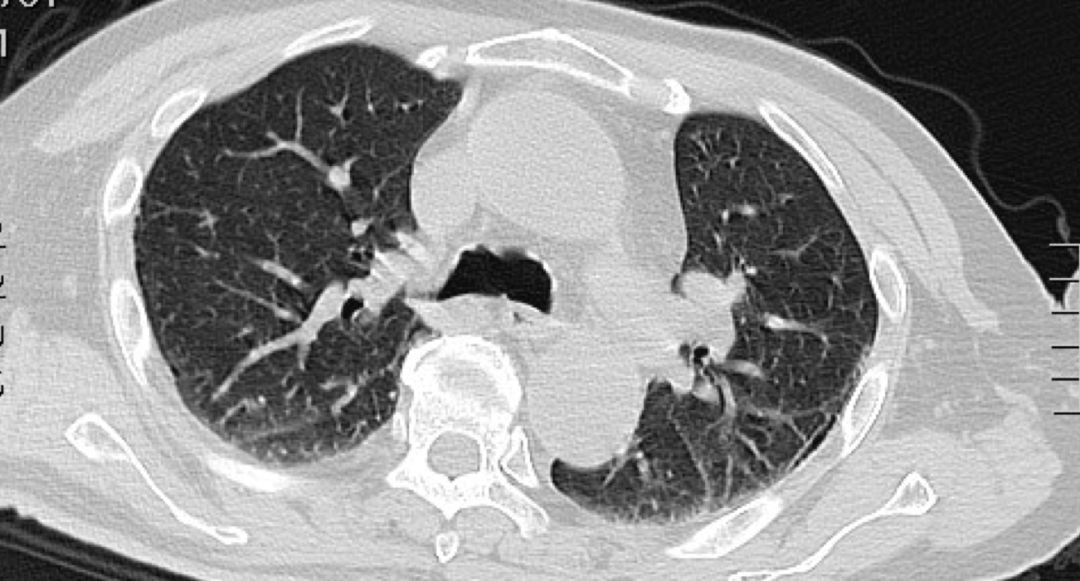

患者女性,66岁,反复咳嗽咳痰近3年。患者近3年来,多次查血沉基本正常,结核抗体阴性,结核杆菌T细胞检测(-),痰x-pert(-)。曾辗转多家医院就诊,均考虑肺结核,拟行抗结核治疗,患者拒绝接受肺结核诊断和抗痨治疗,症状时轻时重,症状重时就自行口服抗生素治疗。病因究竟是什么?是结核感染吗?该如何确诊?肺部CT如下:

左图:患病之初;右图:患病2年7月后

面对病人诉求,我们必须即刻开启病原学精准诊断之路。传统的痰检病原体检测是必须的,同时进行气管镜检查,观察肺内各支气管情况,肺泡灌洗获取下呼吸道标本,进行病原微生物二代基因测序。

非结核分枝杆菌(NTM)(海鱼分枝杆菌)

非结核分枝杆菌非(NTM-PD)的发病率和患病率与日俱增,但是其精准诊断和鉴别诊断一直困扰着临床医师。传统的病原微生物培养技术,面临着培养周期长,敏感性和特异性欠佳之不足。2017年英国胸科协会(BTS)关于NTM管理指南中指出,不应使用口咽拭子培养或血清学检测来诊断 NTM 肺部感染(证据等级 D 级),尚无充分证据推荐常规使用血清学测试来诊断和监测 NTM 肺病患者(证据等级 D 级),皮肤试验和干扰素γ释放试验不应用于疑似 NTM 肺病患者的诊断评估(证据等级 D 级),所有的 NTM 呼吸道样本应通过可靠的分子或质谱技术检测,分离至少达到菌株水平(证据等级 B 级)。可见可靠地检测技术在NTM疾病诊治中占有非常重要的地位,精准医学时代的到来,为临床上这些诊治困难的感染性疾病带来了新曙光。